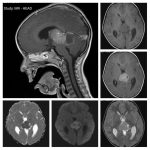

Neurosurgery and neuroradiology always go hand in hand. This little weekly activity is going to enhance the scan reading skills of our audience in an interactive way. Waiting for the answer for a week will keep the curiosity alive and will keep our target audience hooked to the website. It will prove to be a seamless share of knowledge and reading skills.

Dr. Saqib Kamran Bakhshi started the PANS Weekly Image Challenge in 2022, and his creativity and efforts made it a popular activity; engaging trainees and consultants in Pakistan and abroad.